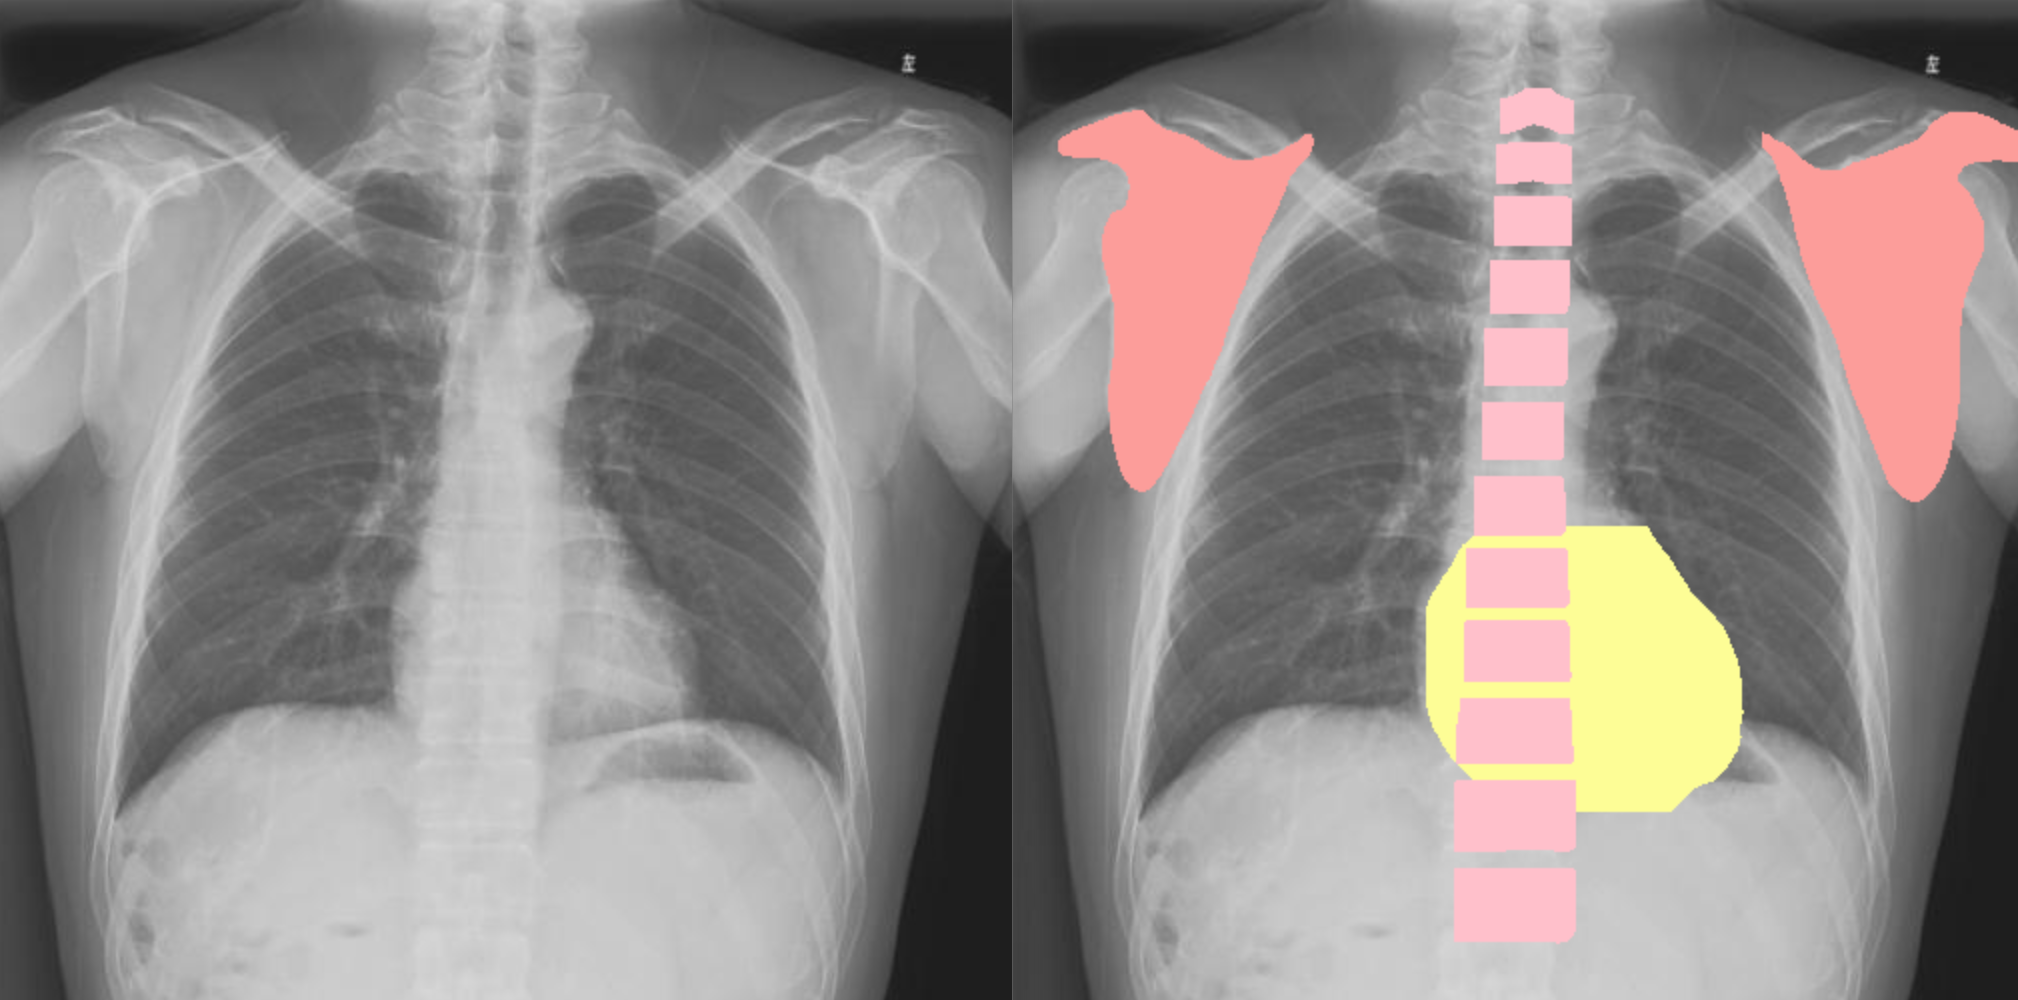

下面是一个正位胸片分割模型的展示,使用 yolov5-seg 进行模型训练,效果也是相当不错